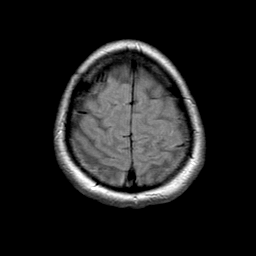

MR Study #1 -- Slice #21

[Home][Help][Clinical][Tour 1] Slice 21